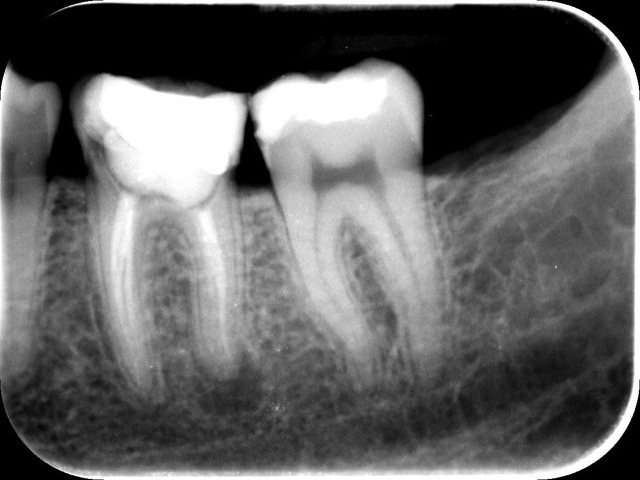

Ryc. 2. Zdjęcie pantomograficzne wykonane przed zabiegiem. Ryc. 3. Zdjęcie zębowe zęba 36.

Wykonano pantomogram oraz zdjęcie celowane, które ujawniło zmianę okołowierzchołkową przy korzeniu dystalnym. Nie stwierdzono patologii tkanek twardych zębów sąsiadujących z zębem zakwalifikowanym do ekstrakcji, dlatego powzięto decyzję o odbudowie implantologicznej przyszłego braku zębowego (ryc. 1-3).